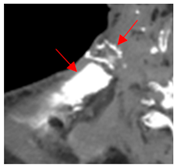

| 3 | 25–50 | 1716 | ![]() Axial CT image shows a mostly necrotic tumor in the right neck. | ![]() Axial CT image obtained 1 day after injection shows the NBTXR3 nanoparticles (arrows) in the tumor with a small amount of leakage into the surrounding soft tissues. |